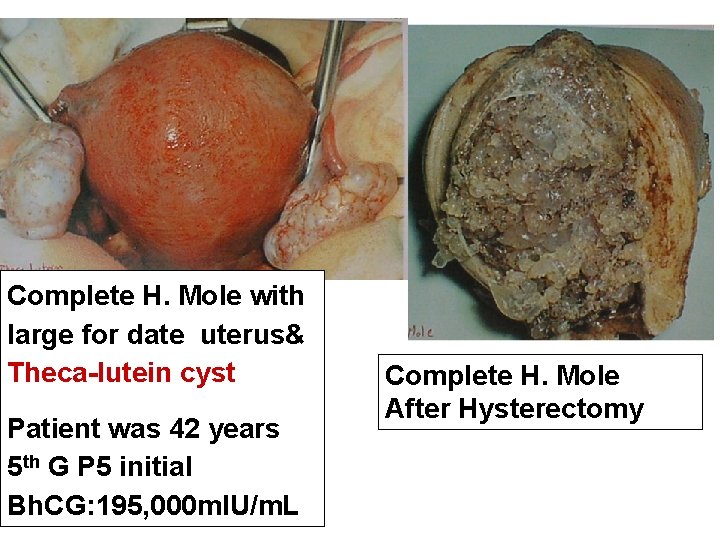

Complete H. Mole with large for date uterus& Theca-lutein cyst Patient was 42 years 5 th G P 5 initial Bh. CG: 195, 000 m. IU/m. L Complete H. Mole After Hysterectomy